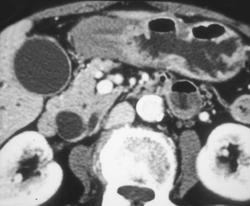

Nonfunctioning Islet Cell Tumor